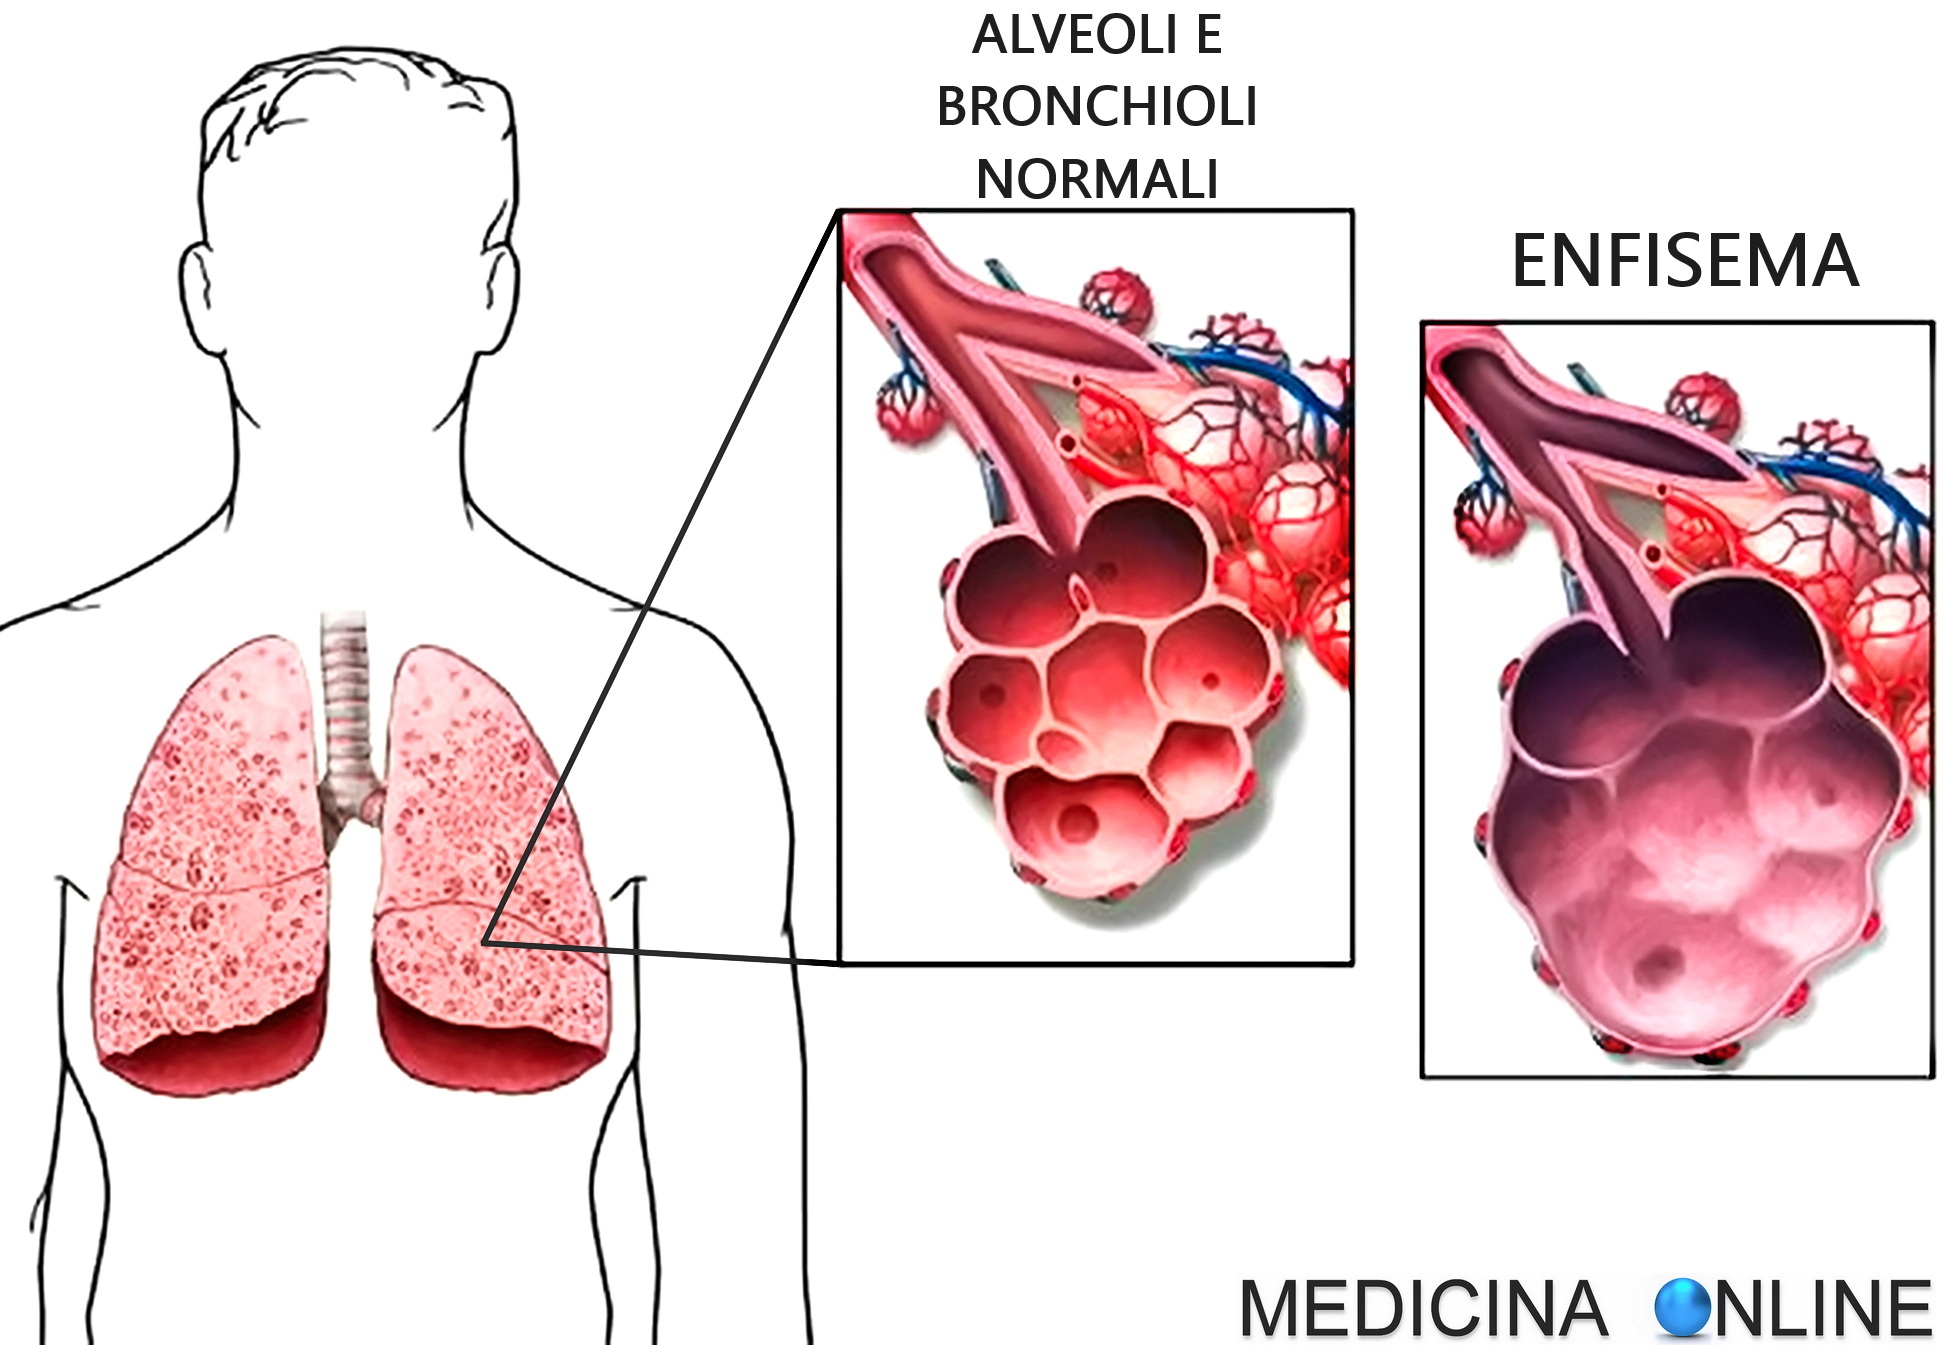

Медицинская тема: легочные осложнения при пневмонии